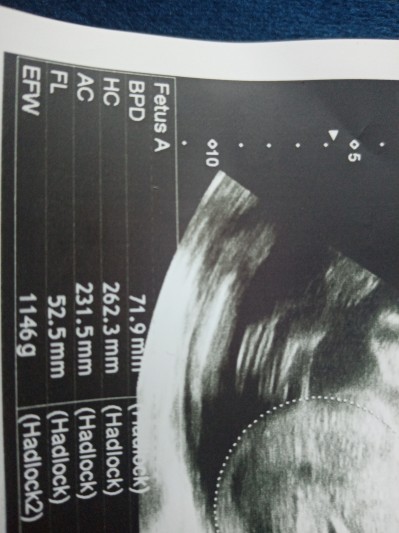

Kızlar anlayanlar varmı bebegin boyu 52 cm mi?

Gebelik haftası 28

O uyluk kemiğinin boyu 5 cm .doktor onu bir şeyler çarpıp söylüyor ama ne olduğunu bilmiyorum:)

Bebek boyu 36,75 cm. Hiç o haftada 52 cm bebek mi olur doğduğunda 1 metre mi olacak :))) Zaten ölçü birimi de milimetre yazmış.

52 mm 7 ile çarpacaksn 36 cm

Hayır bebeğin boyu FL yazan yerdeki sayıyı 0.7 ile çarptığında bebeğin boyunu veriyor sanırım 36 cm gibi birşey oluyor yanılmıyorsam, bildiğim kadarıyla bu şekilde hesaplanıyor :)

Kız 28 haftada 52 cm bebek mi olur :D 7 ile çarpacaksın 36-37 santim falan şuan :))

36 cm olmasi lazim.Fl her zaman  7 le carpilir